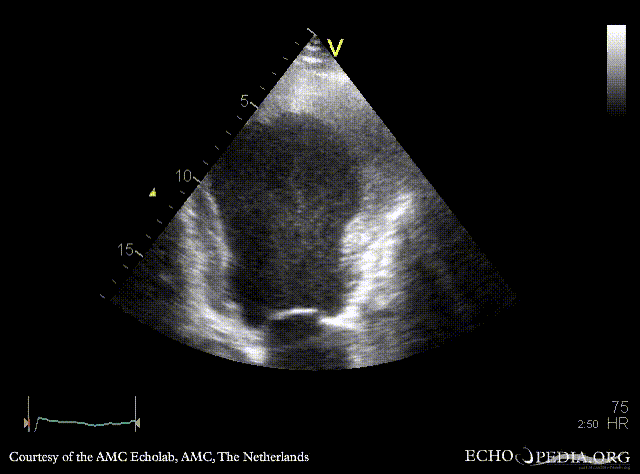

Thrombus in the apex of left ventricle

Courtesy of: AMC Echolab, AMC, The Netherlands

A4CH: dilated left ventricle, poor function, large thrombus in the apex, spontaneous echocontrast A2CH